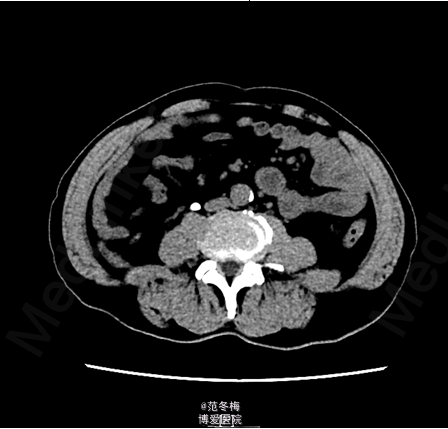

双肾区无红肿、隆起,左肾区叩击痛(+),右肾区叩击痛(+),左侧肋脊点、肋腰点压痛(-),右侧肋脊点、肋腰点压痛(-)。腹平软,左侧输尿管走行区压痛(-),右侧输尿管走行区压痛(-),膀胱区无膨隆,压痛阴性。 入院后完善相关检查,双肾CTU提示右侧输尿管上段结石、炎症;右肾实质萎缩、功能受损。核素肾动态显像提示右肾灌注、功能重度受损;左肾灌注、功能基本正常。

于2015-4-8全麻下行腹腔镜右肾切除术,术后补液对症治疗,病理提示右侧输尿管结石伴肾萎缩。患者术后恢复良好,予出院。